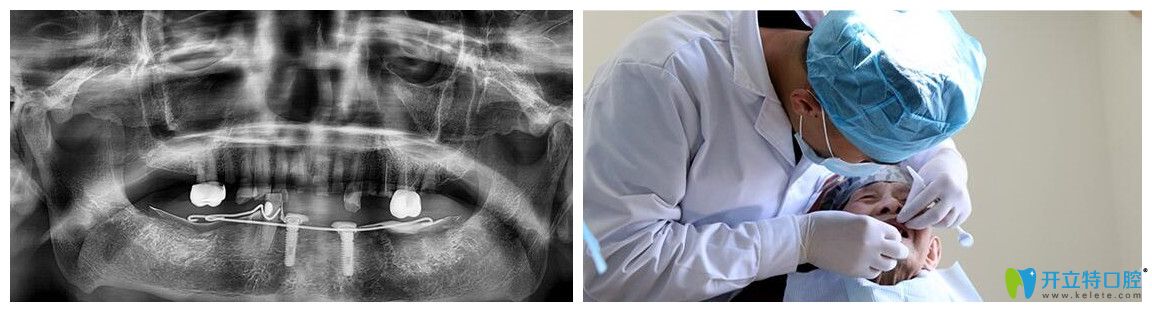

侯主任為韓老實施精準種植手術(shù)圖

術(shù)前,醫(yī)護人員為韓老又進行了一遍CT口腔檢查。侯國鎮(zhèn)主任用“高齡精準種”技術(shù)為韓老實施精準種植手術(shù)。但在韓老進到手術(shù)室的時候,主任察覺到了韓老的緊張感,悄悄鼓勵他:“放輕松,相信我,治療過程很快的,而且也不會有太大的疼痛。”在主任的引導下,韓老狀態(tài)很放松,手術(shù)也很順利的完成了。?

韓老拍CT和醫(yī)生檢查的圖片

術(shù)后CT片顯示,韓老口內(nèi)的種植體植入非常周正、位置和導板設(shè)計完全吻合,手術(shù)非常成功。王明霞醫(yī)生正在給韓老佩戴牙冠修復體。